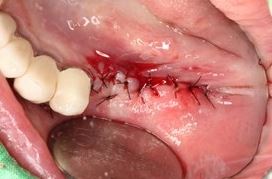

移除感染之植體,解決吸收植體牙周發炎。